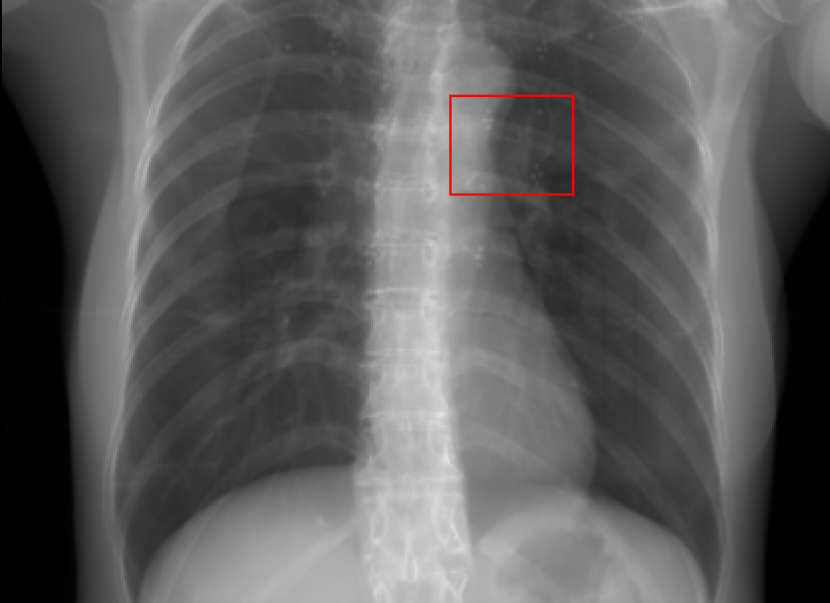

Figure 10: Perspective deformation learning in one exemplary patient case for chest X-ray imaging. The maximal horizontal cardiac diameter and the maximal horizontal thoracic diameter in (b) and (d)-(f) are indicated by the horizontal red lines, while those in the reference image (a) are green lines. The cardiothoracic ratio, RMSE, and SSIM for each image is displayed in its corresponding subcaption.

The results of one patient in chest X-ray imaging are displayed in Fig. 10, where the cardiothoracic ratio is assessed as an exemplary clinical application [32]. In the reference image (Fig. 10(a)), the maximal horizontal cardiac diameter (MHCD) and the maximal horizontal thoracic diameter (MHTD) are indicated by two green horizontal lines. Its cardiothoracic ratio is 0.4237. In the 0superscript00^{\circ} perspective projection image (Fig. 10(b)), all the anatomical structures can be visualized with fine resolution. However, due to perspective deformation, anatomical structures, e.g. the ribs and the spine, are deformed. The deformations are visualized better in the difference image Fig. 10(c). Compared with the ribs and the spine, the heart has less deformation as its location is closer to the isocenter. In Fig. 10(b), the MHCD and the MHTD are indicated by two red horizontal lines, while the green lines are those of the reference image. While the MHCD has changed little from 10.47 cm to 10.16 cm, the MHTD has changed considerably from 24.71 cm to 25.40 cm. As a consequence, the cardiothoracic ratio becomes 0.4002, which is below the normal range of 0.42 - 0.50 [32]. The result of learning perspective deformation from 0superscript00^{\circ} single view is displayed in Fig. 10(d), where the MHCD and the MHTD are 10.63 cm and 24.71 cm, respectively. The MHTD of Fig. 10(d) is the same as that of the reference image. This is also reflected by the difference image Fig. 10(g), where the lower ribs have small errors. However, the upper ribs as well as the spine still have considerable errors. The results of perspective deformation learning from 0&180superscript0superscript1800^{\circ}\&180^{\circ} views in Cartesian and polar coordinates are displayed in Fig. 10(e) and Fig. 10(f), respectively. The measured MHCDs and MHTDs in these two images are very close to the reference ones. Hence, their cardiothoracic ratios, 0.4214 and 0.4240 respectively, are close to the reference ratio as well. In the difference images (Fig. 10(h) and Fig. 10(i)), the errors of ribs and spine decrease as their boundaries are no longer apparently visible. Nevertheless, Fig. 10(i) has less error than Fig. 10(h), achieving the smallest RMSE value of 3.83. The quantitative evaluation of all the 162 testing datasets is displayed in Tab. II, where learning perspective deformation from two complementary views in polar coordinates achieves the least RMSE 4.98 and highest SSIM 0.9517, demonstrating the superiority of learning perspective deformation from two complementary views in polar coordinates.

The TransU-Net results are displayed in Figs. 10(j)-(l). Compared with their corresponding Pix2pixGAN results, the TransU-Net prediction images are more blurry, although the same perceptual loss is used. The error images in Figs. 10(m)-(o) indicate that TransU-Net reduces perspective deformation better with complementary views than a single view. The quantitative evaluation in Tab. II shows that TransU-Net cannot effectively reduce perspective deformation with a single view. With complementary views in both Cartesian and polar coordinate systems, TransU-Net achieves comparable performance, which is still considerably worse than that of Pix2pixGAN. The inferior performance of TransU-Net to Pix2pixGAN on the chest data is potentially caused by the repetitive nature of the segmental rib anatomy, which leads TransU-Net to be ineffective in extracting position-dependent features.